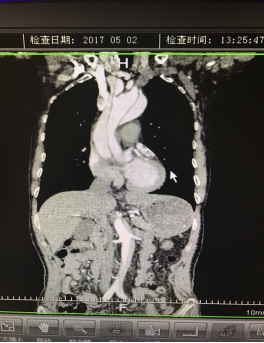

5月2號劉大伯照常早起干活,突然胸部劇烈疼痛,難以忍受,全身大汗,同時伴有右上肢發(fā)涼,他心想這次心絞痛比之前嚴(yán)重的多啊,趕緊叫上孩子到吉林國文醫(yī)院心血管內(nèi)科住院,患者長期高血壓病史,血壓一直控制不理想,大夫給他做了檢查,測左上肢血壓:82/45mmHg,右上肢血壓測不出,心率52次/分,右側(cè)肱動脈、尺動脈、橈動脈搏動消失,左側(cè)股動脈搏動較右側(cè)弱?!霸懔?,雙側(cè)血壓差別這么大,是不是主動脈夾層了?”,接診大夫趕緊找來李主任,李主任反復(fù)詢問患者病情,表情突然凝重起來,患者胸痛這么明顯,血壓低的厲害,主動脈夾層的可能性很大。二話不說,李主任立即聯(lián)系影像科的醫(yī)生準(zhǔn)備做主動脈CTA,移動患者做檢查的過程大夫們非常小心,嚴(yán)密監(jiān)測患者血壓變化情況。兩個小時后結(jié)果出來了,主動脈夾層從升主動脈一直撕裂到左側(cè)髂總動脈!??!